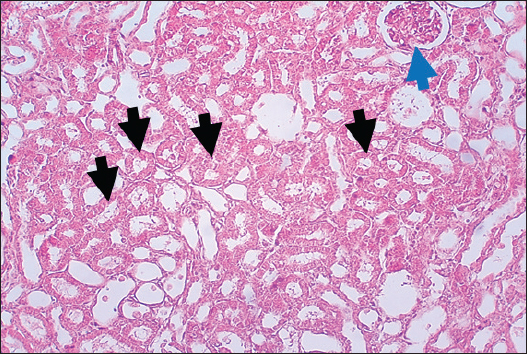

In the control group, histological analysis of kidney sections revealed intact glomeruli and renal tubules (Fig. 1). Conversely, Figure 2 presents a kidney section from the green tea group, which exhibited normal renal tubular epithelial cells, a well-preserved tubular lumen, and an overall normal tubular texture, although some glomeruli showed mild atrophy. The renal section of gentamicin showed atrophy of the glomerular tuft, expansion of the globular space, and significant hyperemia lesions in some glomeruli associated with substantial damage to the superficial cell layer (epithelial cells) in the proximal renal tubules, resulting in a reduction of the tubular lumen space (Fig. 3). In contrast, kidney sections from the gentamicin group that received green tea treatment revealed a marked reveal of both glomeruli and renal tubular epithelium, which appeared normal (Fig. 4 and Fig. 5).

Fig. 1. Rat Kidneys of control rat. The section shows the normal texture of renal tissue (glomeruli, Black arrows) and renal proximal tubules (Red arrows) without any significant occupied lesion. H and E (10X).

Fig. 3. Kidney of gentamicin group. The section shows clear glomerular tuft atrophy (Black arrow) with increasing of glomerular space and sever hyperemia lesion can be seen in some glomeruli (Red arrow). This section explains severe epithelial cells damage in the proximal renal tubules with decreased the tubular lumen space (Blue arrows). H and E (10X).